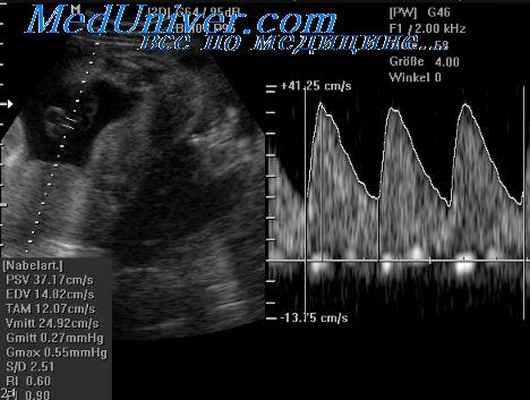

Диагностика. При ультразвуковом исследовании могут обнаруживаться водянка плода (вследствие сердечной недостаточности), с отеком конечностей и гипертрофией их мягких тканей (с превышением показателей размеров окружности над длиной), асцит, патологические гемангиоматоз-ные объемные образования внутрибрюшной локализации, а также гепатомегалия. Описан случай правильного установления диагноза с помощью трехмерной эхографии.